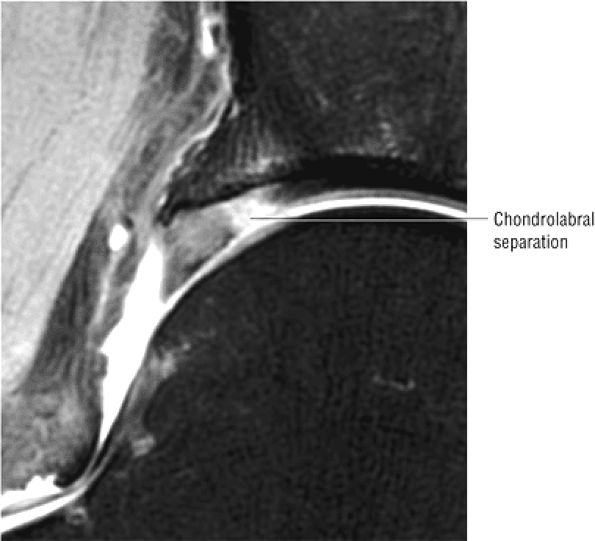

The posterior inferior sublabral sulcus (Fig. 3.60) should not be misinterpreted as a posterior labral tear on axial images.15,16 When depicted, this sublabral groove is seen on one or two axial oblique images superior to the transition between the transverse ligament and the posteroinferior labrum. This sulcus is in fact characterized as a labrocartilaginous cleft and can be shown arthroscopically.

-

An anterosuperior cleft (Fig. 3.61) may be seen as a normal variant in the presence of a normal lateral acetabular labrum. On anterior coronal or sagittal images, this cleft is seen as a partial undercutting of the labrum on a single image. The extension of fluid into this cleft occurs from the femoral side. It may be more commonly seen in labral hypertrophy associated with mild developmental dysplasia of the hip (DDH).

A transverse ligament-labral junction sulcus is a normal sulcus or recess that may be seen between the transverse ligament and the labrum either anteriorly (Fig. 3.62) or posteriorly (Fig. 3.63). The perilabral sulcus (Fig. 3.64) represents a normal space between the acetabular labrum and capsule visualized on coronal images. The capsule attaches directly to the osseous rim of the acetabulum. A normal sulcus may exist at the junction of the transverse ligament and labrum (see Fig. 3.62) on medial sagittal images. A normal perilabral sulcus is present on coronal images between the capsules and labrum and does not represent a pathologic detachment. This sulcus is a distinct and normal potential separation from the labrum (Fig. 3.65). The